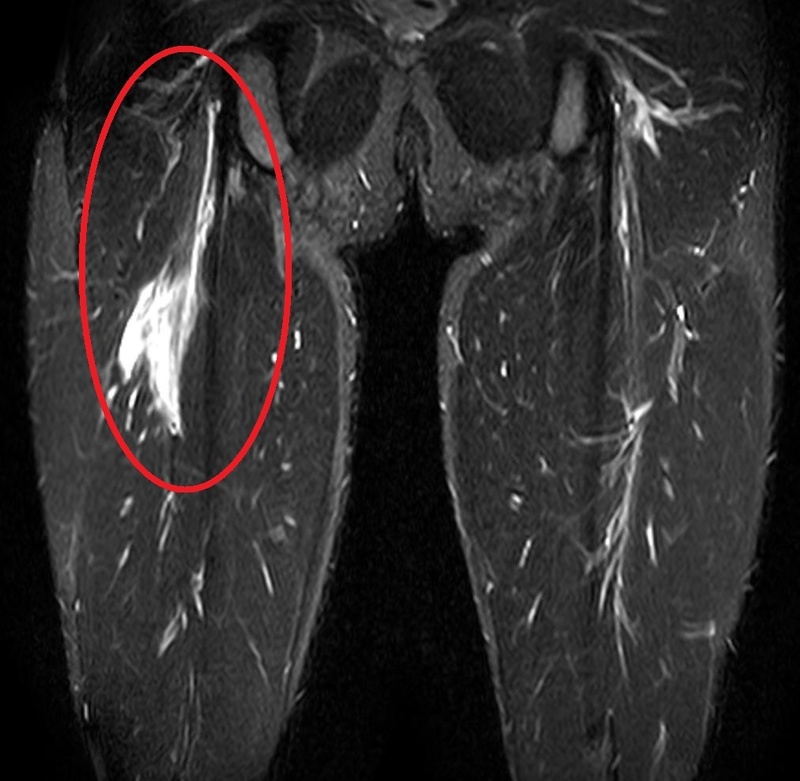

【MRI画像】

赤い丸で囲んである部分の筋肉が損傷し、出血が確認できる(広範囲に白い)